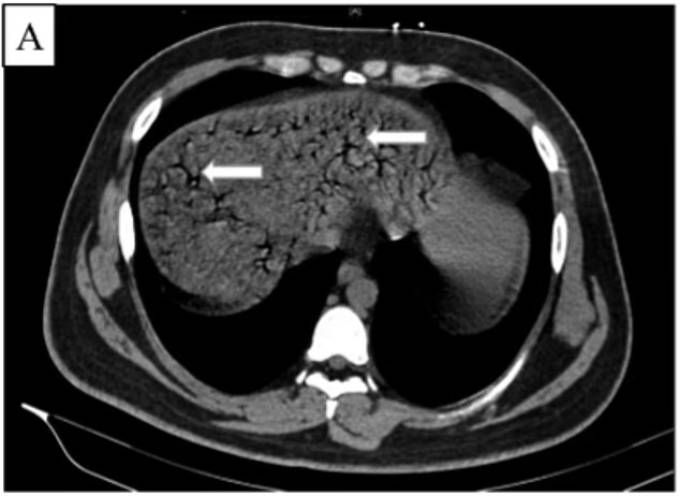

Sau khi kiểm tra, các bác sĩ phát hiện bệnh nhân - người không có bệnh lý nền - bị tăng nhịp tim, huyết áp thấp và thở gấp. Kết quả chụp CT cho thấy nam thanh niên có nồng độ cồn trong thành ruột và tĩnh mạch cửa (bộ phận cung cấp máu đến gan). Chính những điều này đã khiến bệnh nhân bị thiếu máu cục bộ ở gan, còn gọi là "sốc ở gan" - hiện tượng gây ra bởi tình trạng thiếu oxy đến bộ phận này.